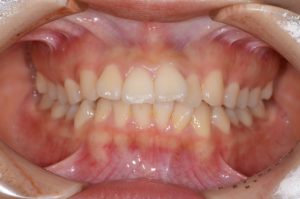

【スプリント治療前】

約4ヵ月間、就寝時にスプリント使用していただきました。

【スプリント治療後】

歯並びは変わっていませんが、顎の位置が正常に安定したことで

噛み合わせの位置が変化していることが分かります。

正しい位置で咬めるようになったためインビザラインに移行します。